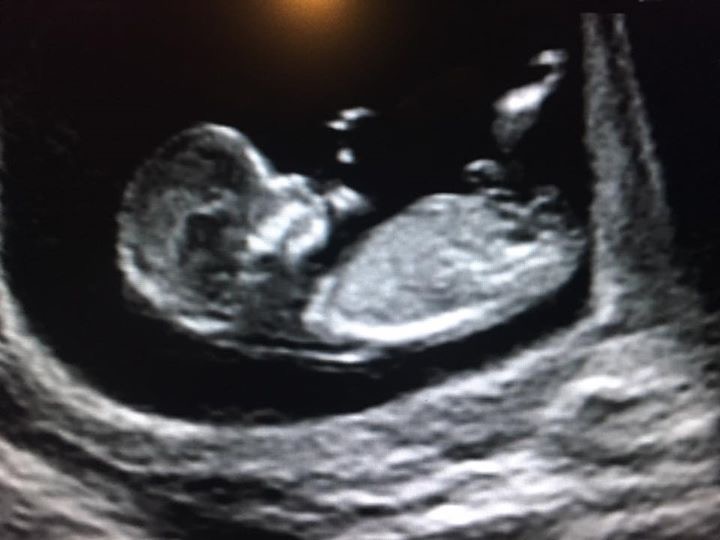

I'm asking for gender guesses for my friend. This is an ultrasound she had at 12wks & 6days.